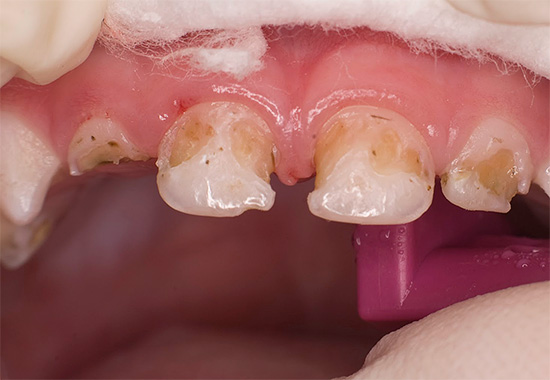

Oggi, a causa della popolarità della cura orale e della disponibilità di servizi dentali, la malattia è diventata meno comune, ma il problema è ancora rilevante nelle aree rurali e nei bambini in età scolare, quando quasi tutti i denti di un bambino sono affetti da carie (vedi l'esempio nella foto), e i genitori non sanno cosa fare in una situazione del genere.

Oltre al fatto che la carie è pericolosa per la salute, provoca dolore e limita la scelta del cibo, è anche un grave problema estetico. La foto sotto mostra un esempio di carie generalizzata: